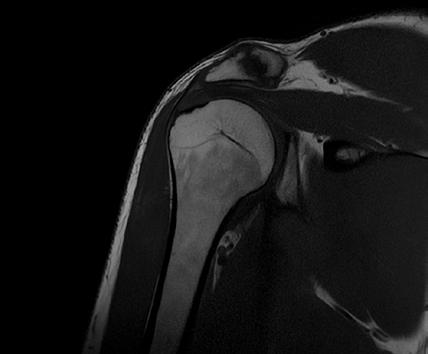

Coronal PD FatSat of the Shoulder, Res: 0.3 x 0.3 x 3 mm, Scan time: 3:25 Original. Same image after AiCE Reconstruction.

Shoulder

16ch Flex SPEEDER, PD, AiCE + Compressed SPEEDER, Res: 0.3 x 0.3 x 3 mm, Scan time: 3:23 min.